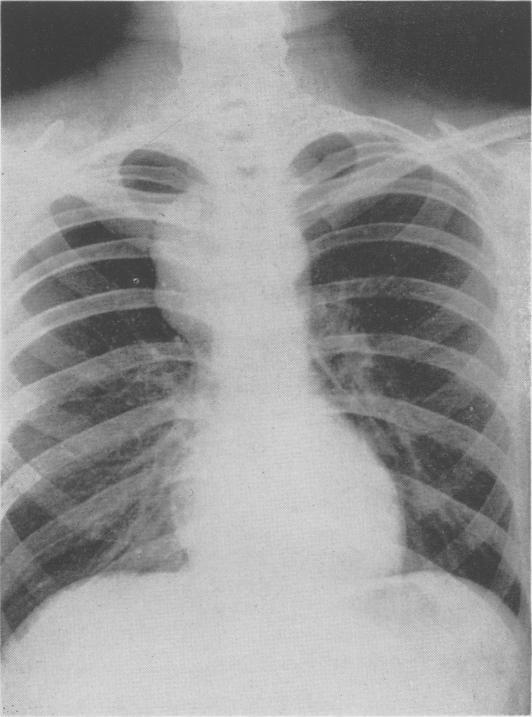

Bronchiogenic Cysts of the Mediastinum.